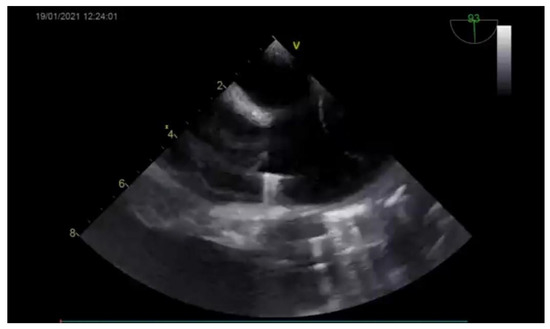

The diagnosis was based on the transthoracic echocardiography (Figure 1 and Figure 2). It revealed an SV-ASD with PAPVD which appeared to open in the right atrium, a dilated right atrium and ventricle, and a left-to-right shunt with Qp:Qs of 2.3 (Qp-pulmonary flow/Qs-systemic flow). The patient had normal pulmonary artery pressure, which was measured during echocardiography.

Figure 2. Preoperative echocardiography (bicaval view) showing the ASD.